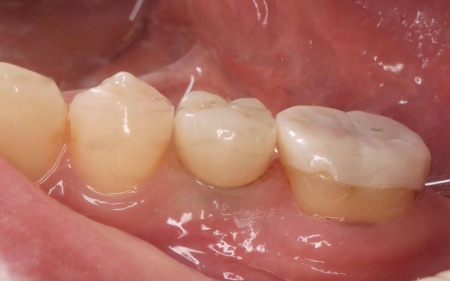

拝見したところ、左上奥歯(第1小臼歯)は歯の上の部分である歯冠が折れ、歯根のみ残っている状態でした。

また、左下奥歯(第2小臼歯)には被せ物が装着されています。

診断結果をお伝えし、患者様の了承を得たうえで左下奥歯の被せ物を外したところ、レントゲン検査での診断どおり、歯根が割れていることが確認できました。

後日、完成した人工歯をインプラントに装着し、使用感や見た目に問題がないことを確認して、治療を終了しました。